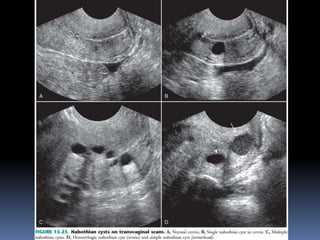

This document contains an image gallery from Dr. Mohit Goel showing various uterine anomalies and ovarian cysts. It includes images of an arcuate and unicornuate uterus, endometritis, a twisted ovarian pedicle, dermoid cysts of varying sizes and echogenicity containing hair, fat, and calcifications, and a combination dermoid cyst showing both mesh and plug structures. The gallery provides ultrasound images of different gynecological conditions for medical education and reference.